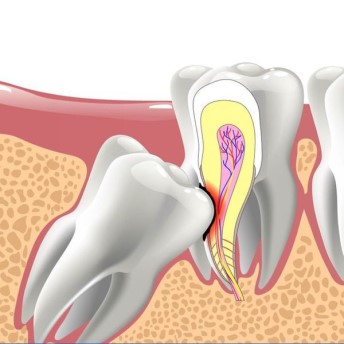

Răng khôn mọc ngang, mọc lệch: Sẽ đẩy vào răng số 7, gây ảnh hưởng cả hàm răng, có thể khiến chân răng số 7 bị ảnh hưởng, gây tiêu xương, viêm nhiễm hoặc nang chân răng

Răng khôn không thể mọc thoát ra ngoài, ngầm trong xương hàm: Sẽ hình thành nang quanh thân răng, nang quanh thân răng phát triển phá hủy toàn bộ xương góc hàm.